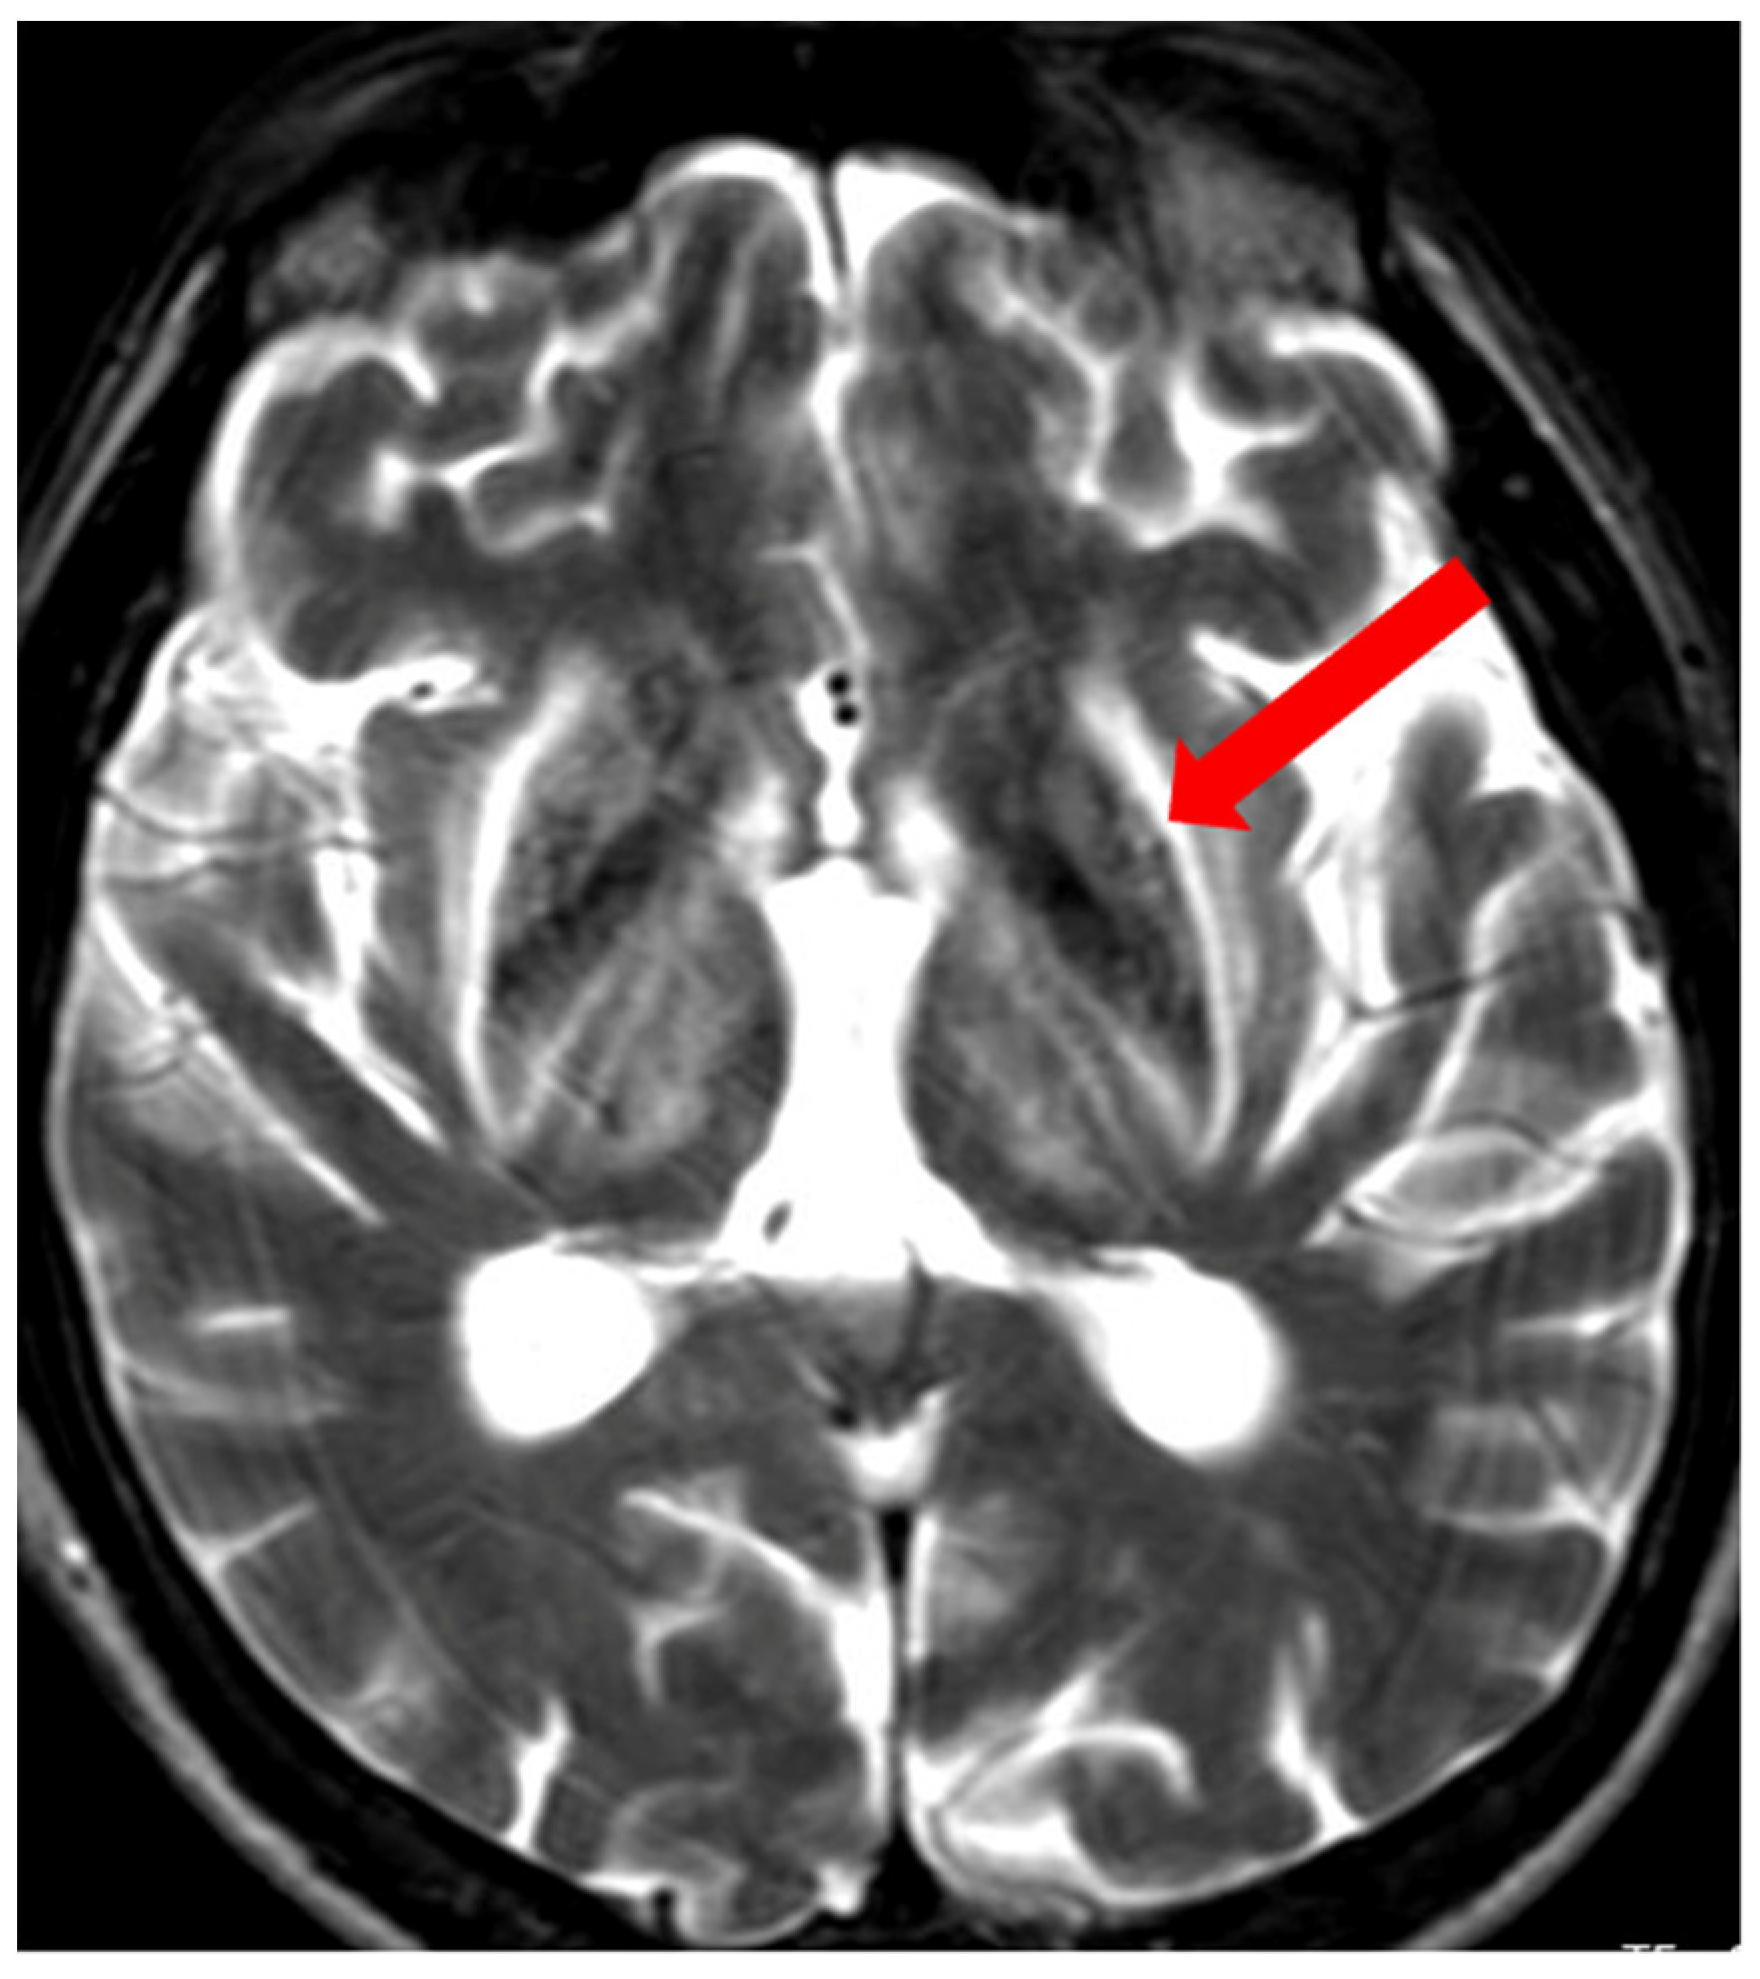

5. Neuroradiological Pathognomonic Signs of WD

- George, U.; Varte, N.; Rathore, S.; Jain, V.; Goyal, S. “Split thalamus”: Internal medullary involvement in Wilson’s disease. Neurol. India 2010, 58, 680. [Google Scholar] [CrossRef] [PubMed]